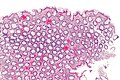

Microscopic

Features:

- Test tube like glands.

- Minimal palisading.

- Nuclei <3:1 = height:width.

- No nuclear pseudostratification. †

- Deep part of crypt is more hyperchromatic than superficial component - important.

- The surface should be lighter staining than the deeper aspect, i.e. the deeper glands are dark blue and the superficial gland are light blue.

Images

- Rectum - low mag.jpg

Rectum - low mag. (WC)

- Rectum - intermed mag.jpg

Rectum - intermed. mag. (WC)

- Rectum - alt - intermed mag.jpg

- Rectum - high mag.jpg

Rectum - high mag. (WC)